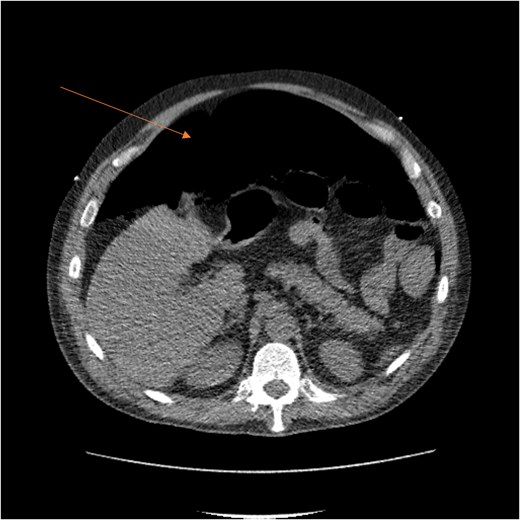

By hospital day 6, the patient’s condition improved. He was weaned from mechanical ventilation, his renal function improved (creatinine declined to 0.7 mg/dl), and hemoglobin stabilized at 8.4 gm/dl. The patient was clinically stable, and on hospital day 8, he was set up for discharge to a rehabilitation institution. However, on this day, he developed generalized abdominal pain associated with tachycardia, pulse = 118, and leukocytosis (white blood cells = 14.8 × 109/l). Physical exam revealed a distended abdomen with diffuse tenderness and sluggish intestinal sounds. A CT scan showed a large volume of pneumoperitoneum, minimal free fluid, and mildly dilated small bowel loops, consistent with a hollow viscus perforation with no identifiable source of perforation (Fig. 5) and a compression of rectosigmoid region against sacral promontory by the enlarged hematoma (Fig. 6). The right colon was decompressed compared with the prior study, and the RSH size remained unchanged, but there was progression of VTE burden. Prior to the acute deterioration, the patient had intermittently reported mild abdominal discomfort, which was initially attributed to the known RSH. There were no clinical signs suggestive of bowel obstruction, such as vomiting or significant abdominal distension. While the patient noted some degree of constipation, he reported that this was consistent with his baseline bowel habits and did not raise concern for new pathology.

CT scan demonstrating pneumo-peritoneum (arrow), indicative of a hollow viscus perforation.